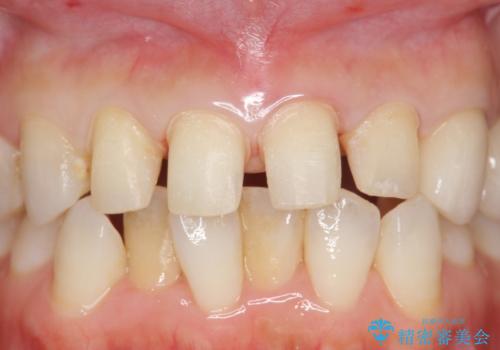

- 保険治療のプラスチックでつぎはぎの歯をセラミックにし、一緒に前歯の並びもきれいにしたいとのご希望でした。

特に裏側のつぎはぎ、二次う蝕(治したところの境目からの虫歯)が多く、審美目的だけでなく、虫歯の治療としても意味があったと思います。

神経を温存するようにあまり削らないように治療しました。